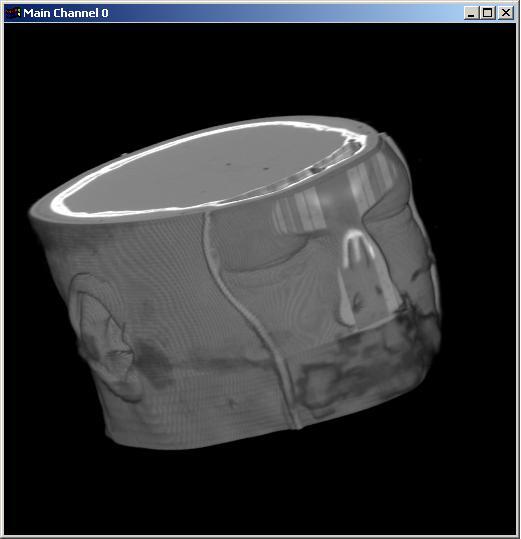

Visible human female CT data

Skin only

Data Resolution : 256x256x128

|

Visible human male CT data

Skin only

Data Resolution : 256x256x128

|

Visible human male CT data

Skin only

Data Resolution : 256x256x128

|

The following 12

images was generated by PC which has NVIDIA's GeForce3 GPU graphics card. The

hardware accelerated rendering techniques are used to make the following images.

To use the GeForce3 hardware, we have to use the OpenGL extensions like

GL_NV_texture_shader2, GL_NV_register_combiners, GL_EXT_texture3D,

GL_EXT_paletted_texture, GL_ARB_multitexture and so on. Since the GeForce3 card

allows the 3D texture shading, the image quality is better than the pixel of

frame buffer based shading in showing two materials at the same time.